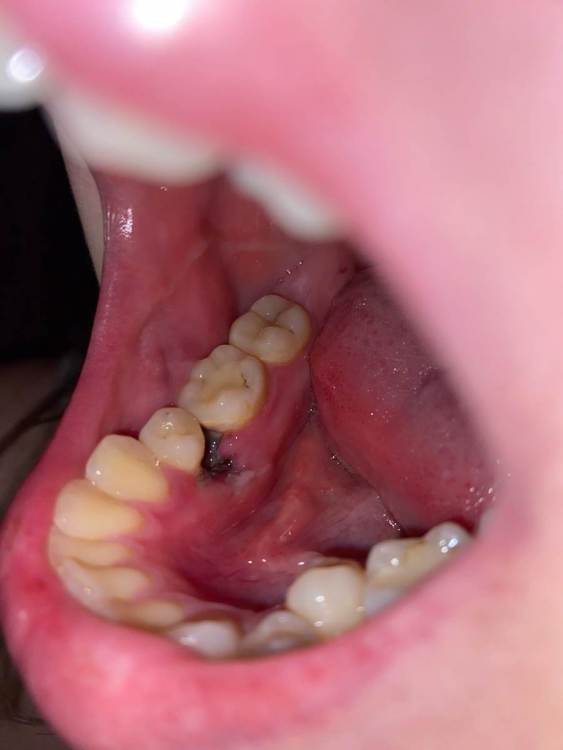

Здравствуйте.Удалили зуб в субботу, сегодня  вторник .Удаление было сложное.Сейчас из симптомов:постоянная пульсирующая боль,боль в ухе , опухшая щека,небольшое увеличение лимфоузлов. Была у врача который делал удаление в понедельник вечером.Посмотрел сказал , хотел залезть во внутрь,решил посоветоваться с другим врачом.и по совету другого врача не стал трогать. Оба молодых парня, почему то не очень вериться  , что это норма

1 фото сразу после Удаления

3 и 5 фото как выглядит все сейч2B56CE66-56D0-4E1D-86A5-4E21849A5812.thumb.jpeg.abaa6f2b73e64da65817873712d3f05f.jpegE0B4CA80-B424-481A-84A3-CF3E12CB7724.thumb.jpeg.6413038171f373f539cc920d011ca1ae.jpegC7227F50-6100-4A26-A12F-E31C37F9D8B0.thumb.png.940d35b1a889de5ed43a9a7bb34ec48f.png1C299E13-97B5-4B9F-97A7-C54C58DB2369.thumb.png.14be377876310f3f10fa0a57b31c5ea7.png743AD060-C0D2-4F96-9EFE-2BF3908D1153.thumb.jpeg.593d27327ab5e07b3e1f53754b9b9614.jpegас